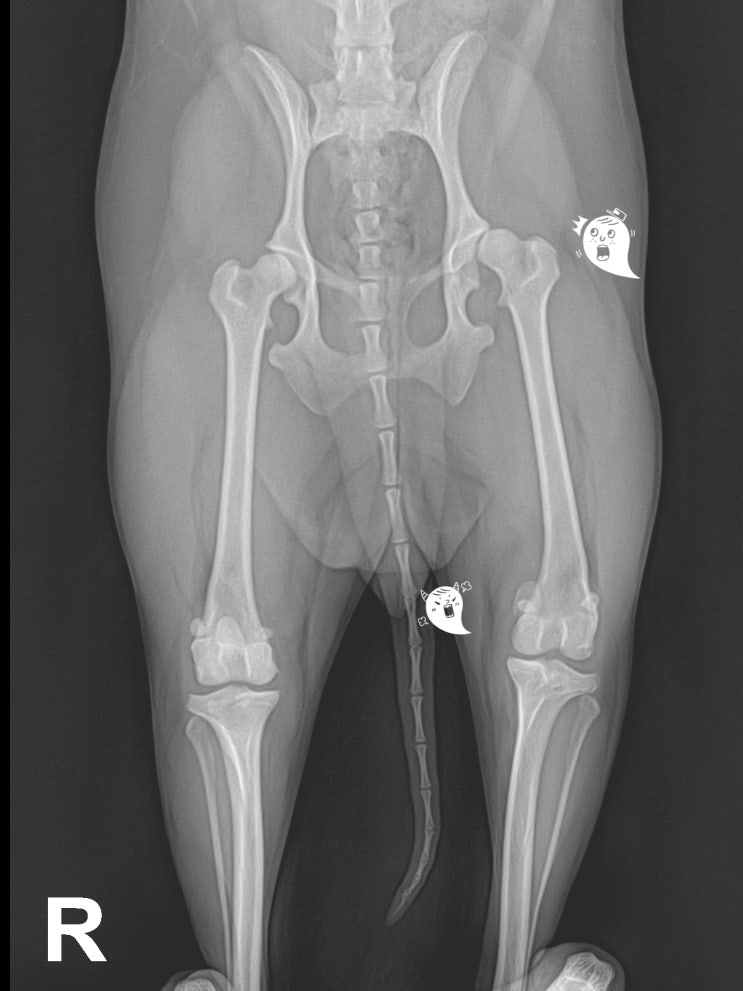

강아지 슬개골 탈구 4 기 수술 8개월 전후 비교 / 반려견 고관절 아탈구 수술 / 애완견 골반 수술 & 슬개골 수술 후유증? / 어린 강아지 무릎 수술 & 관절 주사 치료

안녕하세요~ 굿파파 수의사입니다. 오늘은 여름이 느껴지는 오후네요~ 시원한 커피 한 잔과 함께 ~ 행복한 ...